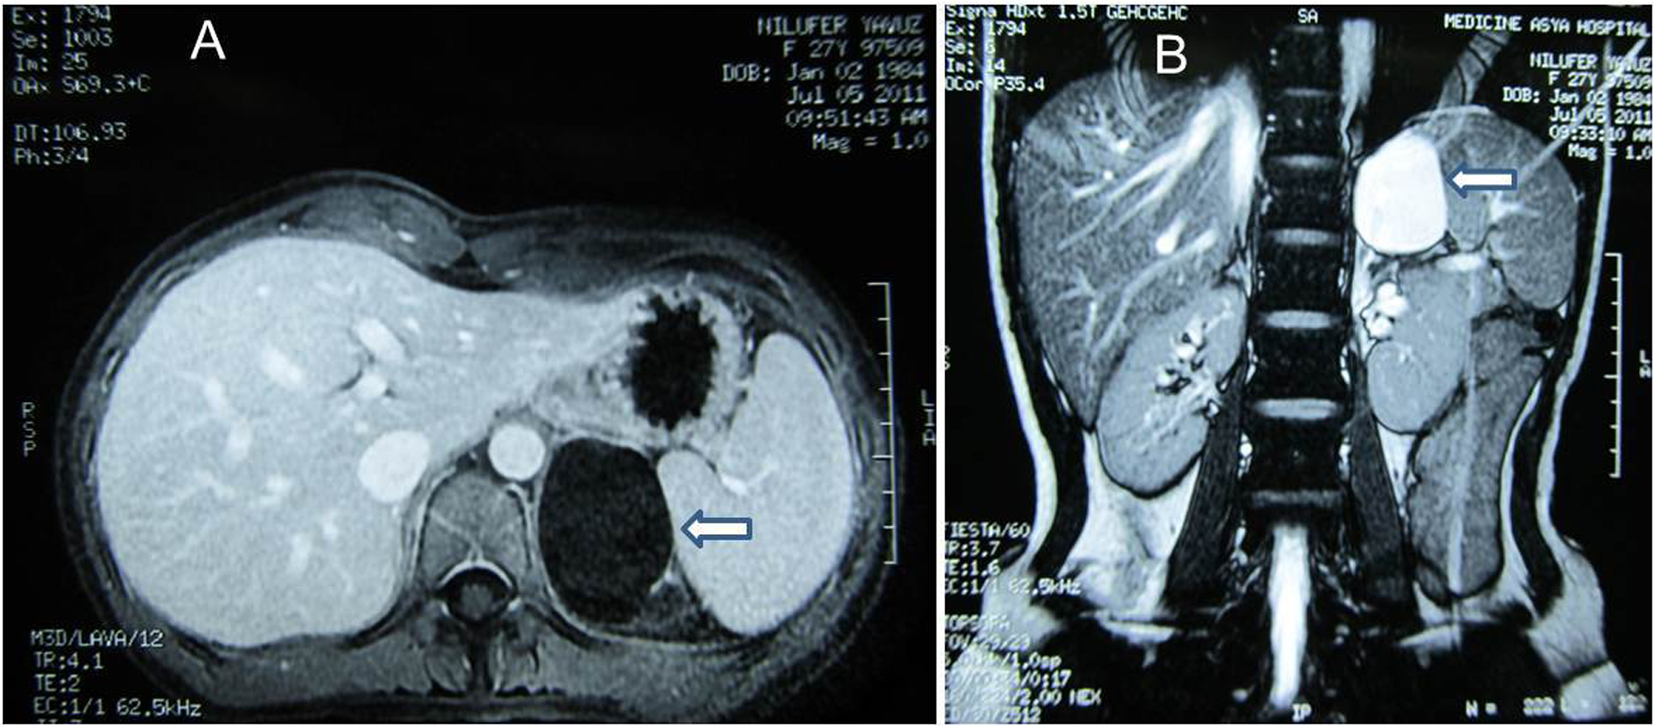

A 27-year-old woman was admitted to the hospital because of a left flank pain. On physical examination, she was normal. Abdominal ultrasonography (USG) revealed a 55 ´ 46 mm cystic mass without any septation or solid component located in the left adrenal space. A laboratory evaluation was done revealing unremarkable values for cortisol (28.12 µg/dL, normal range 5 - 25 µg/dL) and cortisol with 8 mg dexamethasone suppression test (0.35 µg/dL, normal < 3 µg/dL), 24-hour urinary metanephrine (115 µg, normal range 20 - 345 mg) and 24-hour urinary normetanephrine (42.5 µg, normal range 30-440 mg). Magnetic resonance imaging (MRI) of adrenal glands (Fig. 1) was performed demonstrating the 60 mm contrast-enhanced cystic mass in the left adrenal gland.

![]() Click for large image | Figure 1. (A) MRI. Post-contrast axial T1-weighted image demonstrates cystic mass at left suprarenal location (arrow). (B) MRI. Post-contrast coronal breath hold T2-weighted image demonstrates cystic mass of 60 ´ 40 mm in diameter with homogenous high signal intensity (arrow). |